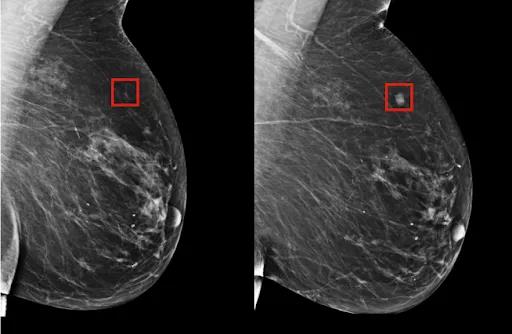

【廣東高尚醫(yī)學(xué)影像】乳腺鉬靶檢查未見(jiàn)癌灶,為何超聲檢查是乳腺癌?

簡(jiǎn)言之,乳腺鉬靶是利用X線成像,對(duì)小鈣化敏感,可以發(fā)現(xiàn)臨床摸不到的乳腺腫塊,尤其是對(duì)于大乳房和脂肪型乳房,其診斷性可高達(dá)95%。也只有憑借乳腺鉬靶檢查,才能對(duì)于以少許微小鈣化為表現(xiàn)的T0期乳腺癌被早期發(fā)現(xiàn)和診斷,這在沒(méi)有任何乳房問(wèn)題以及癥狀的女性中尤為適用。

但由于乳腺鉬靶是二維成像,腺體致密的時(shí)候,會(huì)出現(xiàn)造成漏診和誤診的可能。比如,對(duì)于在乳房表面附近發(fā)現(xiàn)的腫塊,容易受到重疊組織干擾,就會(huì)出現(xiàn)漏診情況。但在某些情況下,乳房超聲檢查比鉬靶檢查能夠更好地檢測(cè)乳腺癌。超聲檢查對(duì)年輕女性、致密型乳腺均較理想,可以更好的檢測(cè)到這些遺漏。